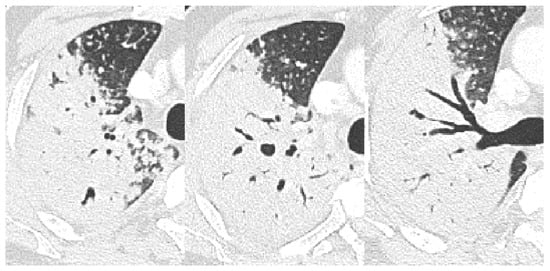

| Bronchial erosion | 157 (47) | 110 (44) | 9 (30) | 38 (73) | <0.001 | 0.157 | <0.001 | <0.001 |

| Cavitation | 157 (47) | 109 (43) | 7 (23) | 41 (79) | <0.001 | 0.038 | <0.001 | <0.001 |

| Consolidation/macronodule | 294 (89) | 221 (87) | 25 (83) | 48 (92) | 0.452 | 0.566 † | 0.313 | 0.276 † |

| Bronchovascular bundle thickening | 249 (74) | 184 (73) | 21 (70) | 44 (85) | 0.172 | 0.752 | 0.072 | 0.116 |